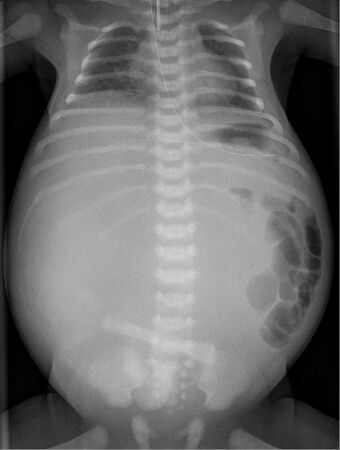

X-ray of a newborn with meconium pseudocyst resulting from bowel perforation. In this case the cause was atresia of the terminal ileum. There is a fine rim of calcification surrounding the big pseudocyst which shifts the other intestinal structures outwards.

Twenty percent of infants born with meconium peritonitis will have vomiting and dilated bowels on x-rays which necessitates surgery[citation needed].

Meconium peritonitis is sometimes diagnosed on prenatal ultrasound[1] where it appears as calcifications[2] within the peritoneum.